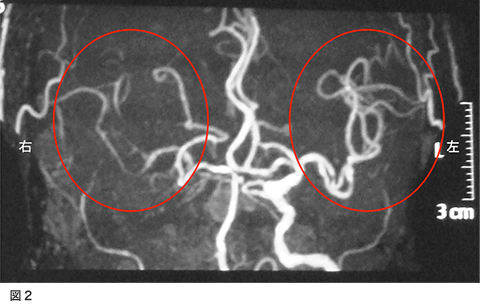

脳の血管が急につまって倒れてしまう病気が脳梗塞です。脳梗塞は様々な原因があるのですが、その一つとして頚部内頚動脈狭窄があります。これは糖尿病、高血圧症、喫煙、高脂血症といった生活習慣病が動脈硬化を来たし、頚部の内頚動脈が細くなり、ここに血栓(小さな血のかたまり)が形成され血液の流れに乗って脳まで流れて脳の血管を詰まらせる、または血管が細くなることで脳の血の巡りが悪くなり脳梗塞を発症します(図1左、図2)。

検査は頚動脈エコー、頸部血管MRA、または血管撮影などがあります。この検査の選択は各施設によって異なります。これらの検査で強い動脈狭窄が発見されたら患者さんと相談して手術治療を考えていくことになります。この手術を頚動脈内膜血栓摘出術(CEA)といいます。簡単に説明すると、動脈硬化で細くなった血管を広げて、脳梗塞の原因となる血の塊(血栓)を取り去ってしまう手術です(図1、図3)。現在最も安全性と治療効果に優れている方法です。この手術の適応で興味のあるところは施設の手術成績によって適応が決定されることです。症状が出現した内頚動脈狭窄症に対してはCEAの合併症が6%以下の施設での手術が有効性であるとされています。別の言い方をするとCEAの合併症が6%以上の施設、術者はこの手術をやってはいけないことになります。